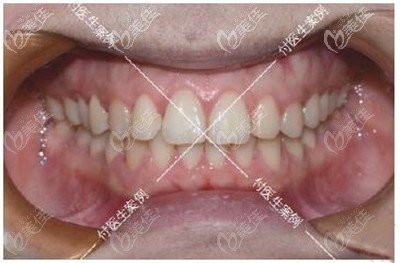

我做牙齿矫正一共花了差不多500多天,看我矫正后的效果,牙齿咬合调整好了,之前反颌的牙齿也归队了,重点是没想要深覆合做牙齿矫正真的会对脸型有影响!

我现在下巴出来了,笑起来更舒展了,再也不怕会露牙龈了。身边的朋友多怀疑我去做了整形,问我是不是悄咪咪的垫下巴了!哈哈,反正这个矫正效果我真的很满意,现在的侧面弧度我真的爱了。